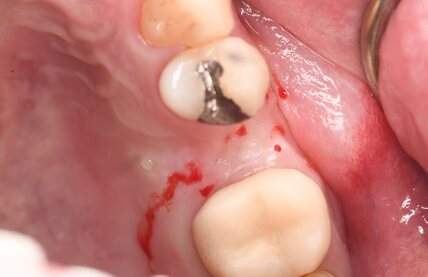

症例写真-1

- Befor

- After

症例写真-2

- 途中経過

| 年齢 | 50代・男性 |

| 主訴 | 右下歯が疼く |

| 治療内容 | ・右下6番インプラント ※1:FGG(遊離歯肉移植術)とは、足りない歯ぐきを上顎から上皮を切り取り移植する外科手術 |

| 治療費 | 合計:902,000円(税込) ■内訳 |

| 治療期間 | 9ヵ月 |

| 治療方針 | 右下の当該歯は歯根破折により保存不可能と診断しました。歯周疾患も伴っていたため抜歯後に骨吸収※1が大きく起こることが予測できました。チタンメッシュ併用骨再生誘導法(GBR※2)を選択しインプラント埋入と同時に行い自然な歯槽骨のラインを再現しました。またGBRを行う際にインプラント辺縁の付着歯肉の減少が起こる為、遊離歯肉移植術(FGG※3)を行い清掃性を考慮した形態に仕上げました。 ■治療方針の解説 治療した右下の歯をレントゲンで撮影したところ根本の部分に黒く写る箇所があり「根尖性慢性周囲炎※1」と診断。また歯周病も進行していました。 ※1 骨吸収・・・歯槽骨という歯を支える骨がなくなっていくこと |

| 担当者所見 | 主訴の右下だけでなく歯茎の腫れ、発赤があり不良補綴や不良充填など他にも治療箇所が多数ありました。プラークコントロールが不良であった為まずはブラッシング指導を行いセルフケアの重要性を理解していただくところからスタートしました。 右下6番の歯はインプラント治療を行なった結果審美的にも機能的にも患者様の満足を得ることができました。骨造成と歯肉移植も行なった為インプラントを支える十分な歯周組織の獲得ができたと思っております。 |